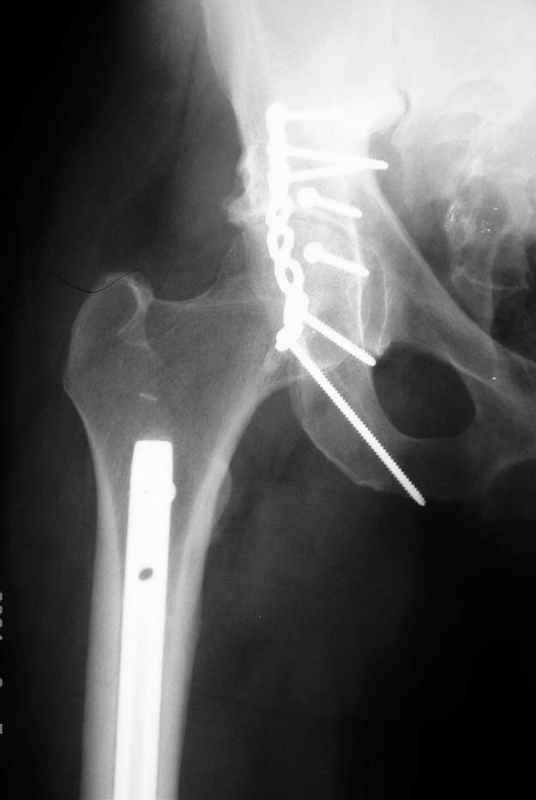

К сожалению, набора для ретроградного или антеградного реконструктивного штифтования в операционной нет, поэтому доставка заняла н-ное время. Вопрос, который возник у меня- по поводу оптимальной тактики хирургии: вся фиксация в один этап из расширенного доступа или последовательно сначала бедро и позже реконструкция впадины, комбинированный доступ к впадине отдельно к передней и задней колоннам или из расширенного илеофеморального одного доступа. Все-таки решил остановиться на одноэтапном подходе и спустя 5 дней (как раз и наборы привезли) из расширенного илеофеморального доступа сначала фиксировал реконструктивным штифтом Smith&Nephews бедро и

шейку (благо перелом шейки 2 типа -относительно стабильный) затем фрагмент крыла подвздошной кости Lag screw, далее пластина на заднюю колонну и винты в переднюю колонну.(с размерами и направлением винтов ошибка вышла:-((, но интраоперационно у меня была полная уверенность , что винты *ушли* в лонную кость).

Еще раз спасибо за комментарии и готовность помочь с имплантами. Постоп картинки в приложении,

Пластина на обе колонны и Lag screw с передней к задней, тактика правильная.